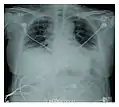

Radiographie montrant une réduction marquée de la capacité pulmonaire_Idiopathic_DAD_3.jpg.webp)

La progression rapide des symptômes initiaux à l'insuffisance respiratoire est une caractéristique clé. Le diagnostic s'appuie sur une tomodensitométrie (TDM) permettant d'écarter les autres causes de lésion aigüe du poumon[3]. Une biopsie du poumon qui montre l'organisation de lésions alvéolaires diffuses peut aussi être pratiquée. D'autres tests de diagnostic sont utiles pour exclure d'autres conditions similaires, mais l'histoire, la radiographie et la biopsie sont essentielles. Ces autres tests peuvent inclure des analyses sanguines de base, des hémocultures et un lavage bronchoalvéolaire.